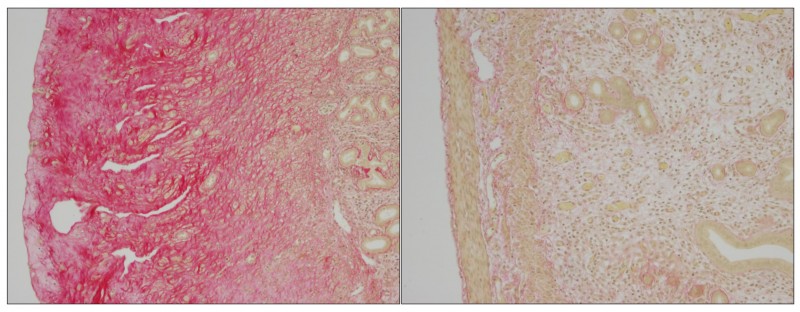

Accumulation de matériel extracellulaire dans un utérus de souris. © EPFL

Des scientifiques de l'EPFL ont identifié le mécanisme biologique derrière le Syndrome de la fibromatose hyaline, maladie défigurante, douloureuse et potentiellement mortelle. Légende de l'image: L'absence d' ANTXR2 conduit à l'accumulation de matériel extracellulaire dans l'utérus des souris, ce qui les rend stériles (à gauche). La suppression du collagène 6 dans les souris n'exprimant pas ANTXR2 conduit à la restauration de la structure et fonction de l'utérus (à droite). Ceci indique que c'est bien l'accumulation de collagène 6 qui est responsable de la disruption du tissu utérin en l'absence d'ANTXR2, ce dernier jouant donc un rôle crucial dans la dégradation du collagène 6. Le Syndrome de la fibromatose hyaline (HFS) est une maladie génétique rare mais grave, qui affecte les bébés, les enfants et les adultes. Une substance vitreuse nommé hyaline s'accumule dans la peau et divers organes du patient, provoquant des déformations douloureuses et pouvant conduire à une mort prématurée. La maladie est provoquée par des mutations génétiques qui détruisent la fonction d'une protéine dont la fonction physiologique est mal connue.